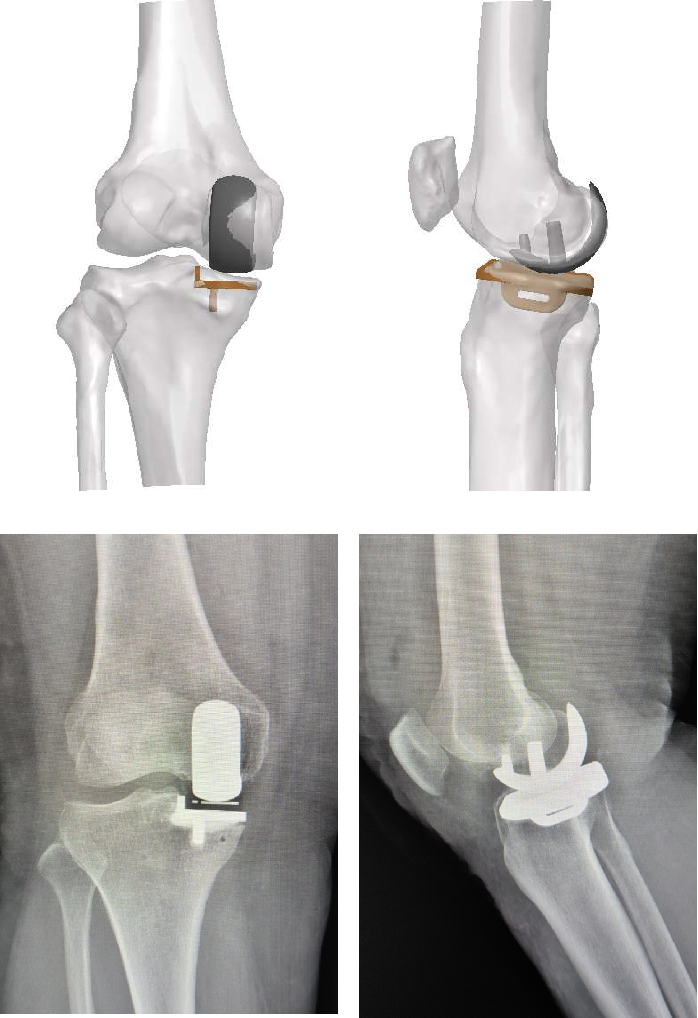

图片

不同案例——术中截骨块对比